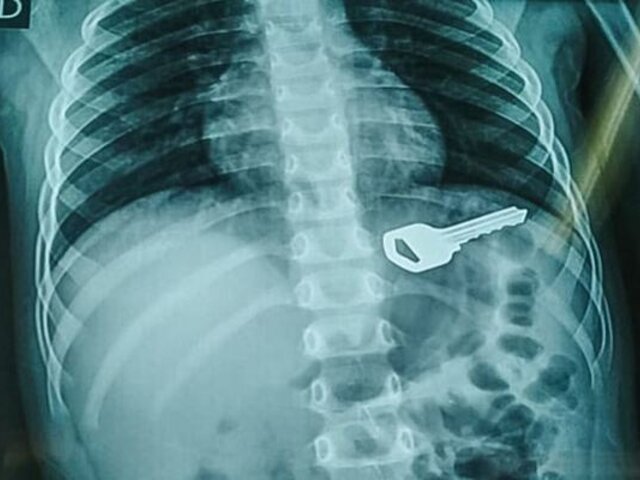

Asimismo, en Huánuco, recientemente los profesionales de la salud pudieron salvarle la vida a un pequeño de tan solo cuatro años, tras intervenirlo quirúrgicamente para sacarle una llave de cinco centímetros.

Sobre este caso y cómo llegó el cuerpo extraño al organismo del menor, la doctora Edith Altamirano, contó que el menor estaba jugando en su vivienda cuando ingirió el objeto.